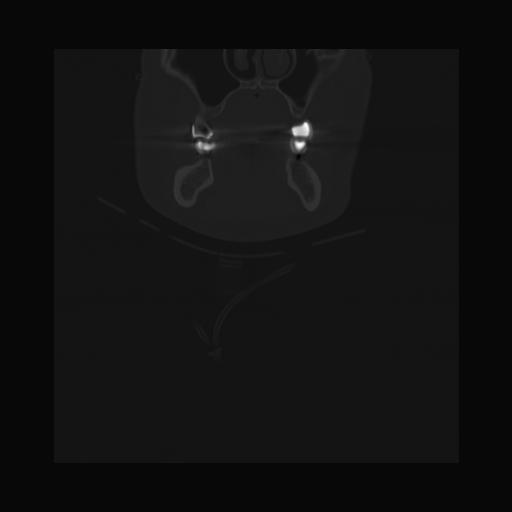

16 HUESO,,Coronal,2.000,HUESO,Coronal,